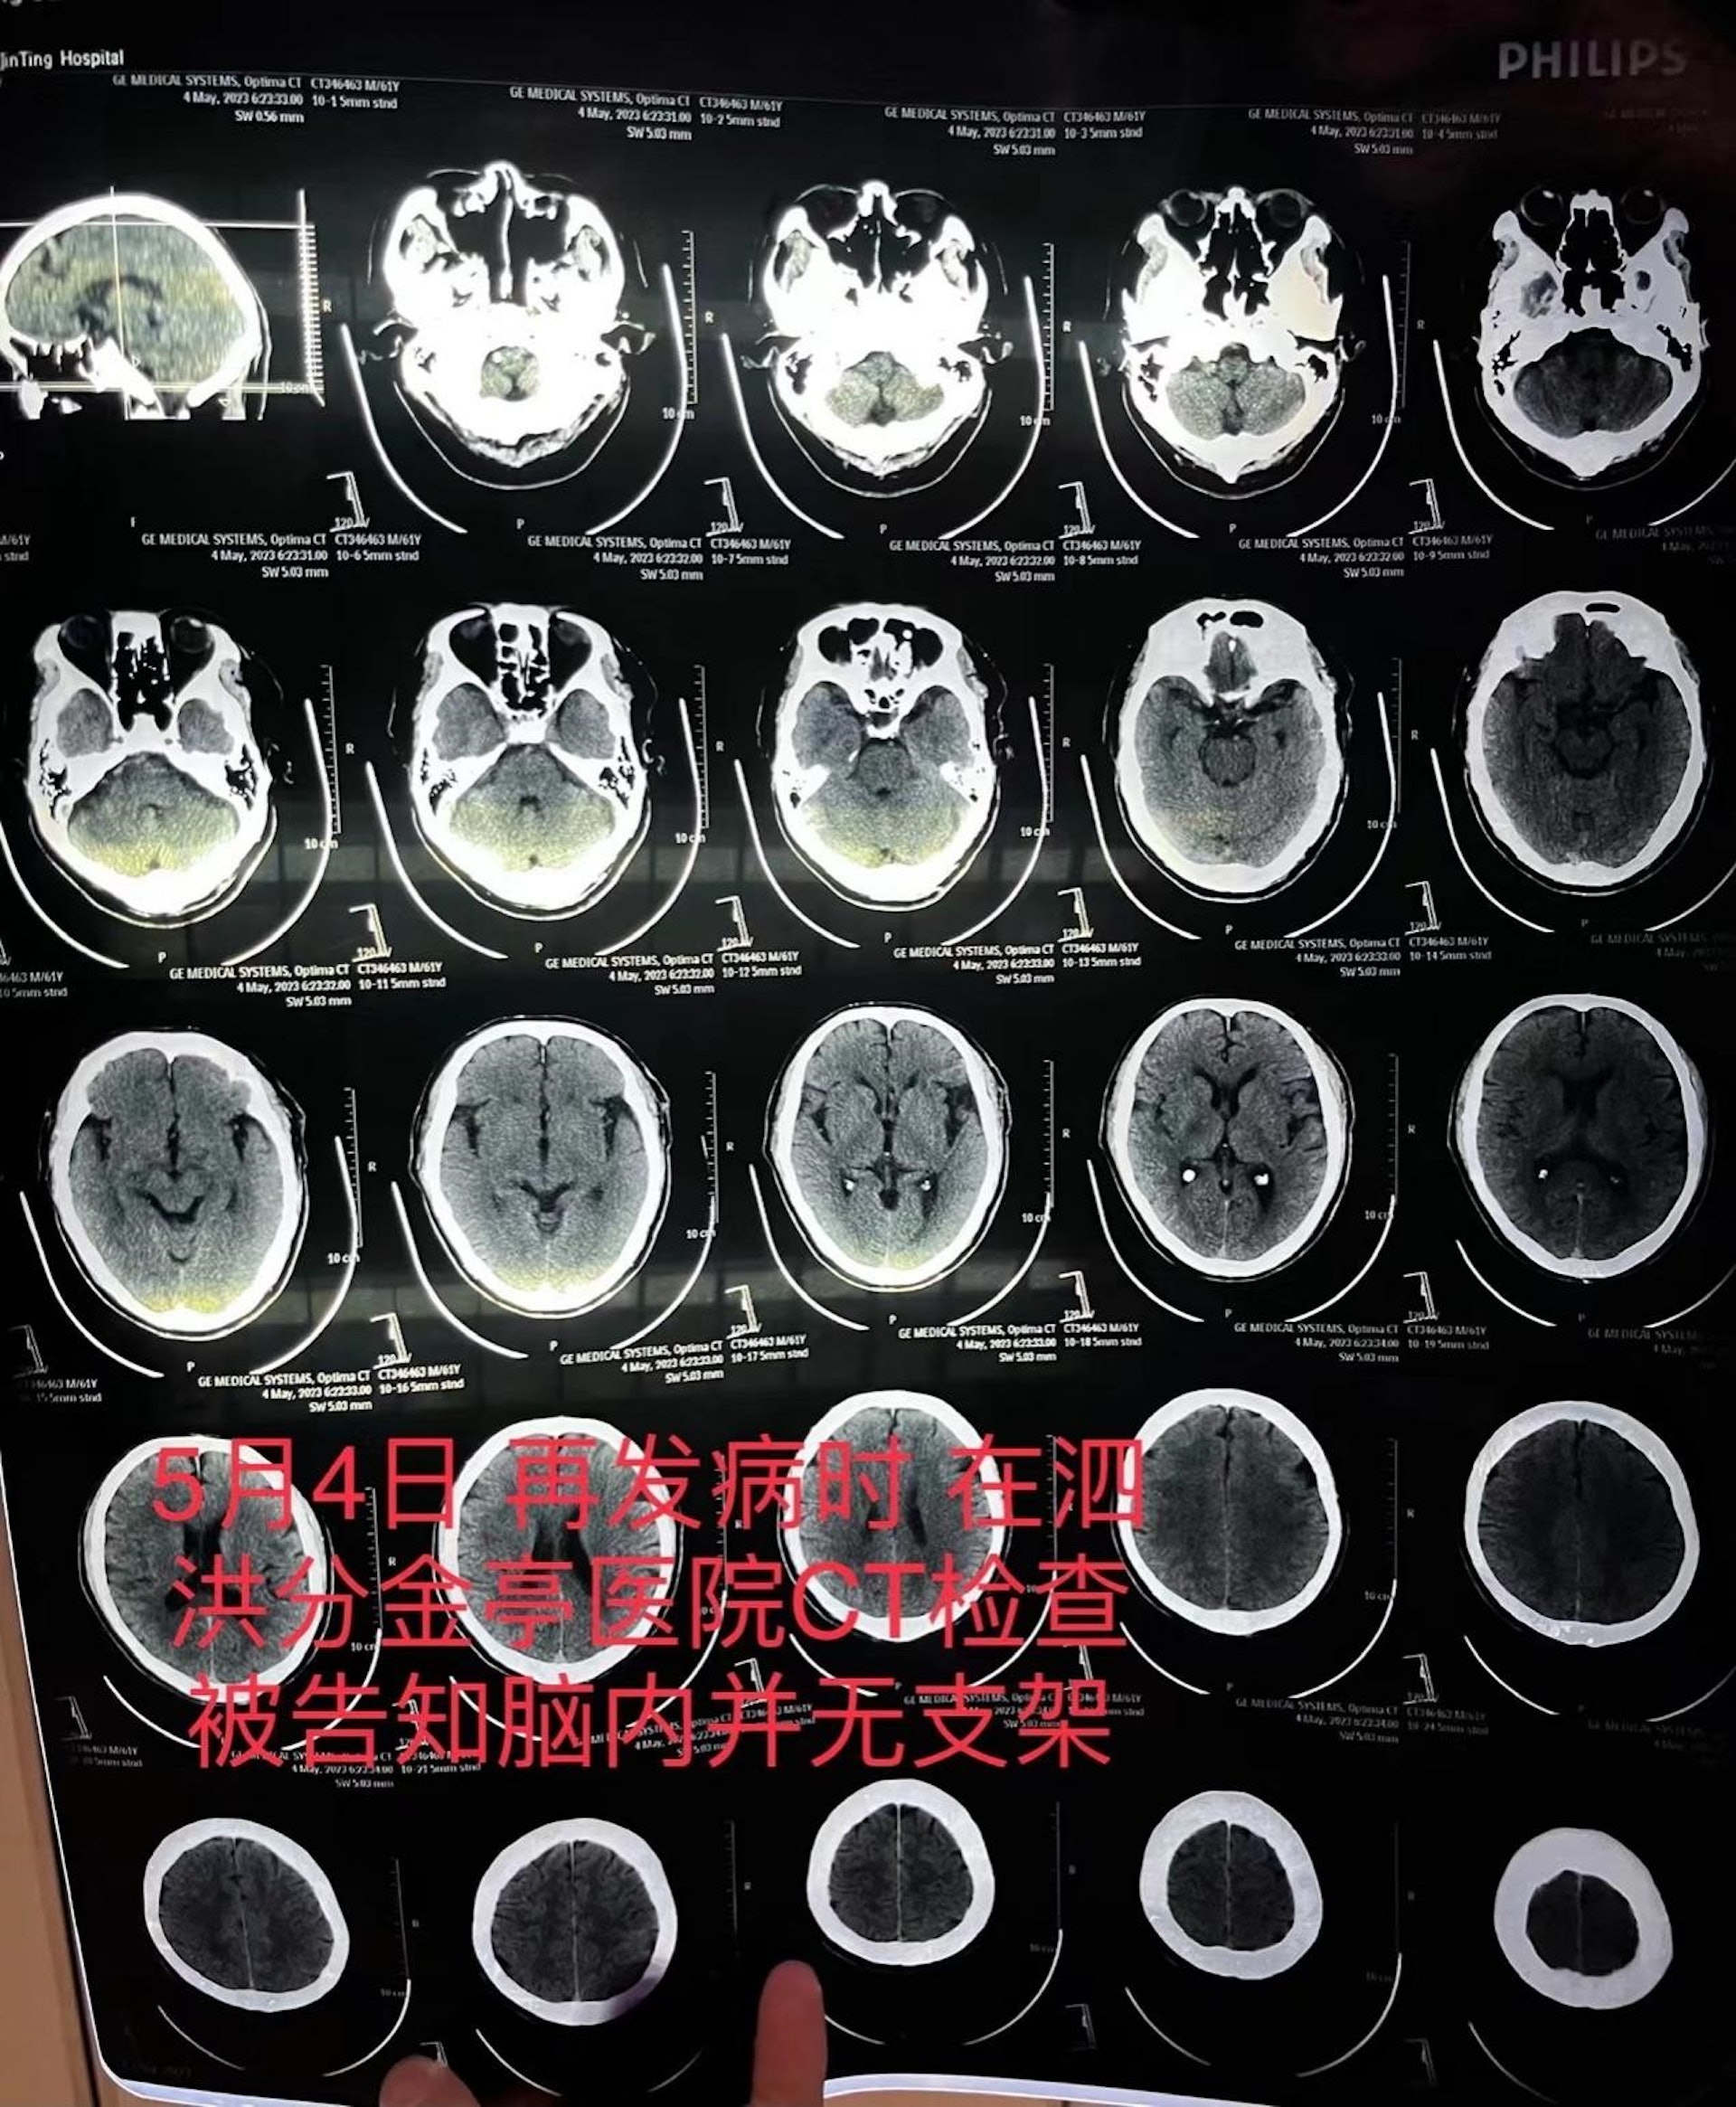

6 s" ^( ?! D! N! wtvb now,tvbnow,bttvb可是才過約一個月,朱父於5月4日突發嚴重腦梗,被送至宿遷市泗洪縣分金亭醫院搶救。這時家屬才透過CT檢查發現,其顱內段部分動脈已嚴重堵閉,此前植有的支架更「消失」了。& [( U0 N' W$ e k4 B% q; I

$ [/ l1 D' i! w: C* X/ e; B9 Ytvb now,tvbnow,bttvbCT檢查報告顯示朱父顱內並無支架。(澎湃新聞)TVBNOW 含有熱門話題,最新最快電視,軟體,遊戲,電影,動漫及日常生活及興趣交流等資訊。6 j3 `5 V4 k6 s3 X$ |8 D